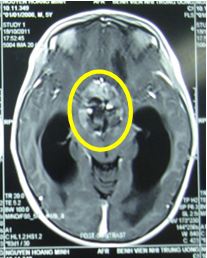

Trước điều trị: Hình ảnh chụp cộng hưởng từ (MRI) sọ não: là u sọ hầu (Vùng tổn thương trong vòng màu vàng; Vùng dãn não thất trong vòng màu xanh nhạt)

• Kế hoạch xạ trị: xạ trị gia tốc với liều 27Gy/15 buổi; Phân liều: 1,8Gy/ngày, trong 3 tuần.